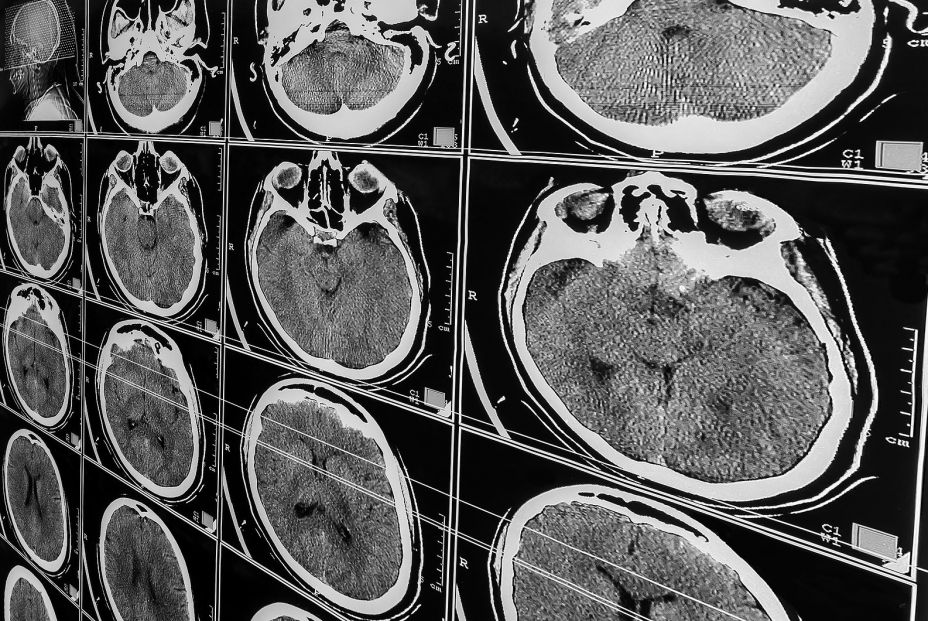

La ciencia ha alcanzado un hito muy importante en la lucha contra las enfermedades neurodegenerativas. Un grupo internacional de científicos ha dado a conocer la base de datos más amplia jamás creada sobre biomarcadores proteicos, un recurso que promete transformar tanto el diagnóstico temprano como el diseño de tratamientos para enfermedades como el párkinson, alzhéimer, demencia frontotemporal y esclerosis lateral amiotrófica (ELA).

Esta iniciativa es liderada por el científico español Carlos Cruchaga desde su laboratorio en la Universidad de Washington en San Luis (EEUU), y sus hallazgos han sido publicados en cinco artículos de las revistas Nature Medicine y Nature Aging. Esta nueva base de datos reúna más de 250 millones de mediciones únicas de proteínas, obtenidas de aproximadamente 40.000 muestras de plasma sanguíneo y líquido cefalorraquídeo de personas de distintas partes del mundo.

Los científicos han logrado identificar más de 2.000 proteínas vinculadas con el alzhéimer, el párkinson y la demencia frontotemporal. Utilizando distintas técnicas de inteligencia artificial, seleccionaron las diez más relevantes para cada una, lo que permite establecer comparaciones entre ellas y con los perfiles de personas con envejecimiento normal.

Este hallazgo representa un avance muy importante hacia diagnósticos menos invasivos. Hasta el momento, los biomarcadores se detectaban mayoritariamente en el líquido cefalorraquídeo, un proceso más complejo. El hallazgo de marcadores en sangre marca una amplia mejora en términos de accesibilidad y prevención.